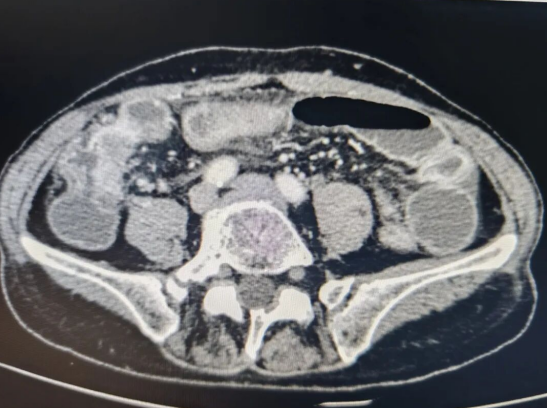

CT显示回盲部梗阻

家人立即带着张阿姨转至西安高新医院。CT检查后,结果却出乎意料,张阿姨并非阑尾炎,而是回盲部肿瘤引发的肠梗阻,而且肿瘤侵犯到右侧卵巢、腰大肌,并且出现多发肝转移。